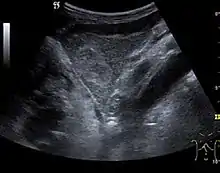

Regenerative nodule (CEUS). One can see the hypovascular pattern of the solid nodule, with a size <10 mm.

These lesions are well defined, with isoechoic or hypoechoic appearance and sizes less than 1 cm. They are high in numbers and have a more or less uniform distribution, involving all liver segments. They can crowd resulting in large pseudo tumors. At Doppler examination, these nodules have no circulatory signal. CEUS exploration is indicated when a nodule is different against the general pattern of restructured liver either by different echogenity or by a different size than the majority of nodules. During the arterial phase, the signal is weak or absent. During the portal venous and late phase, the appearance is persistently isoechoic.

Generally, RN is not distinct from the surrounding parenchyma. CEUS examination is useful to exclude an active lesion at the moment of exploration but does not have absolute prognostic value; therefore the patient should be periodically examined at short intervals. Correlation with clinical status and AFP measurements is required.